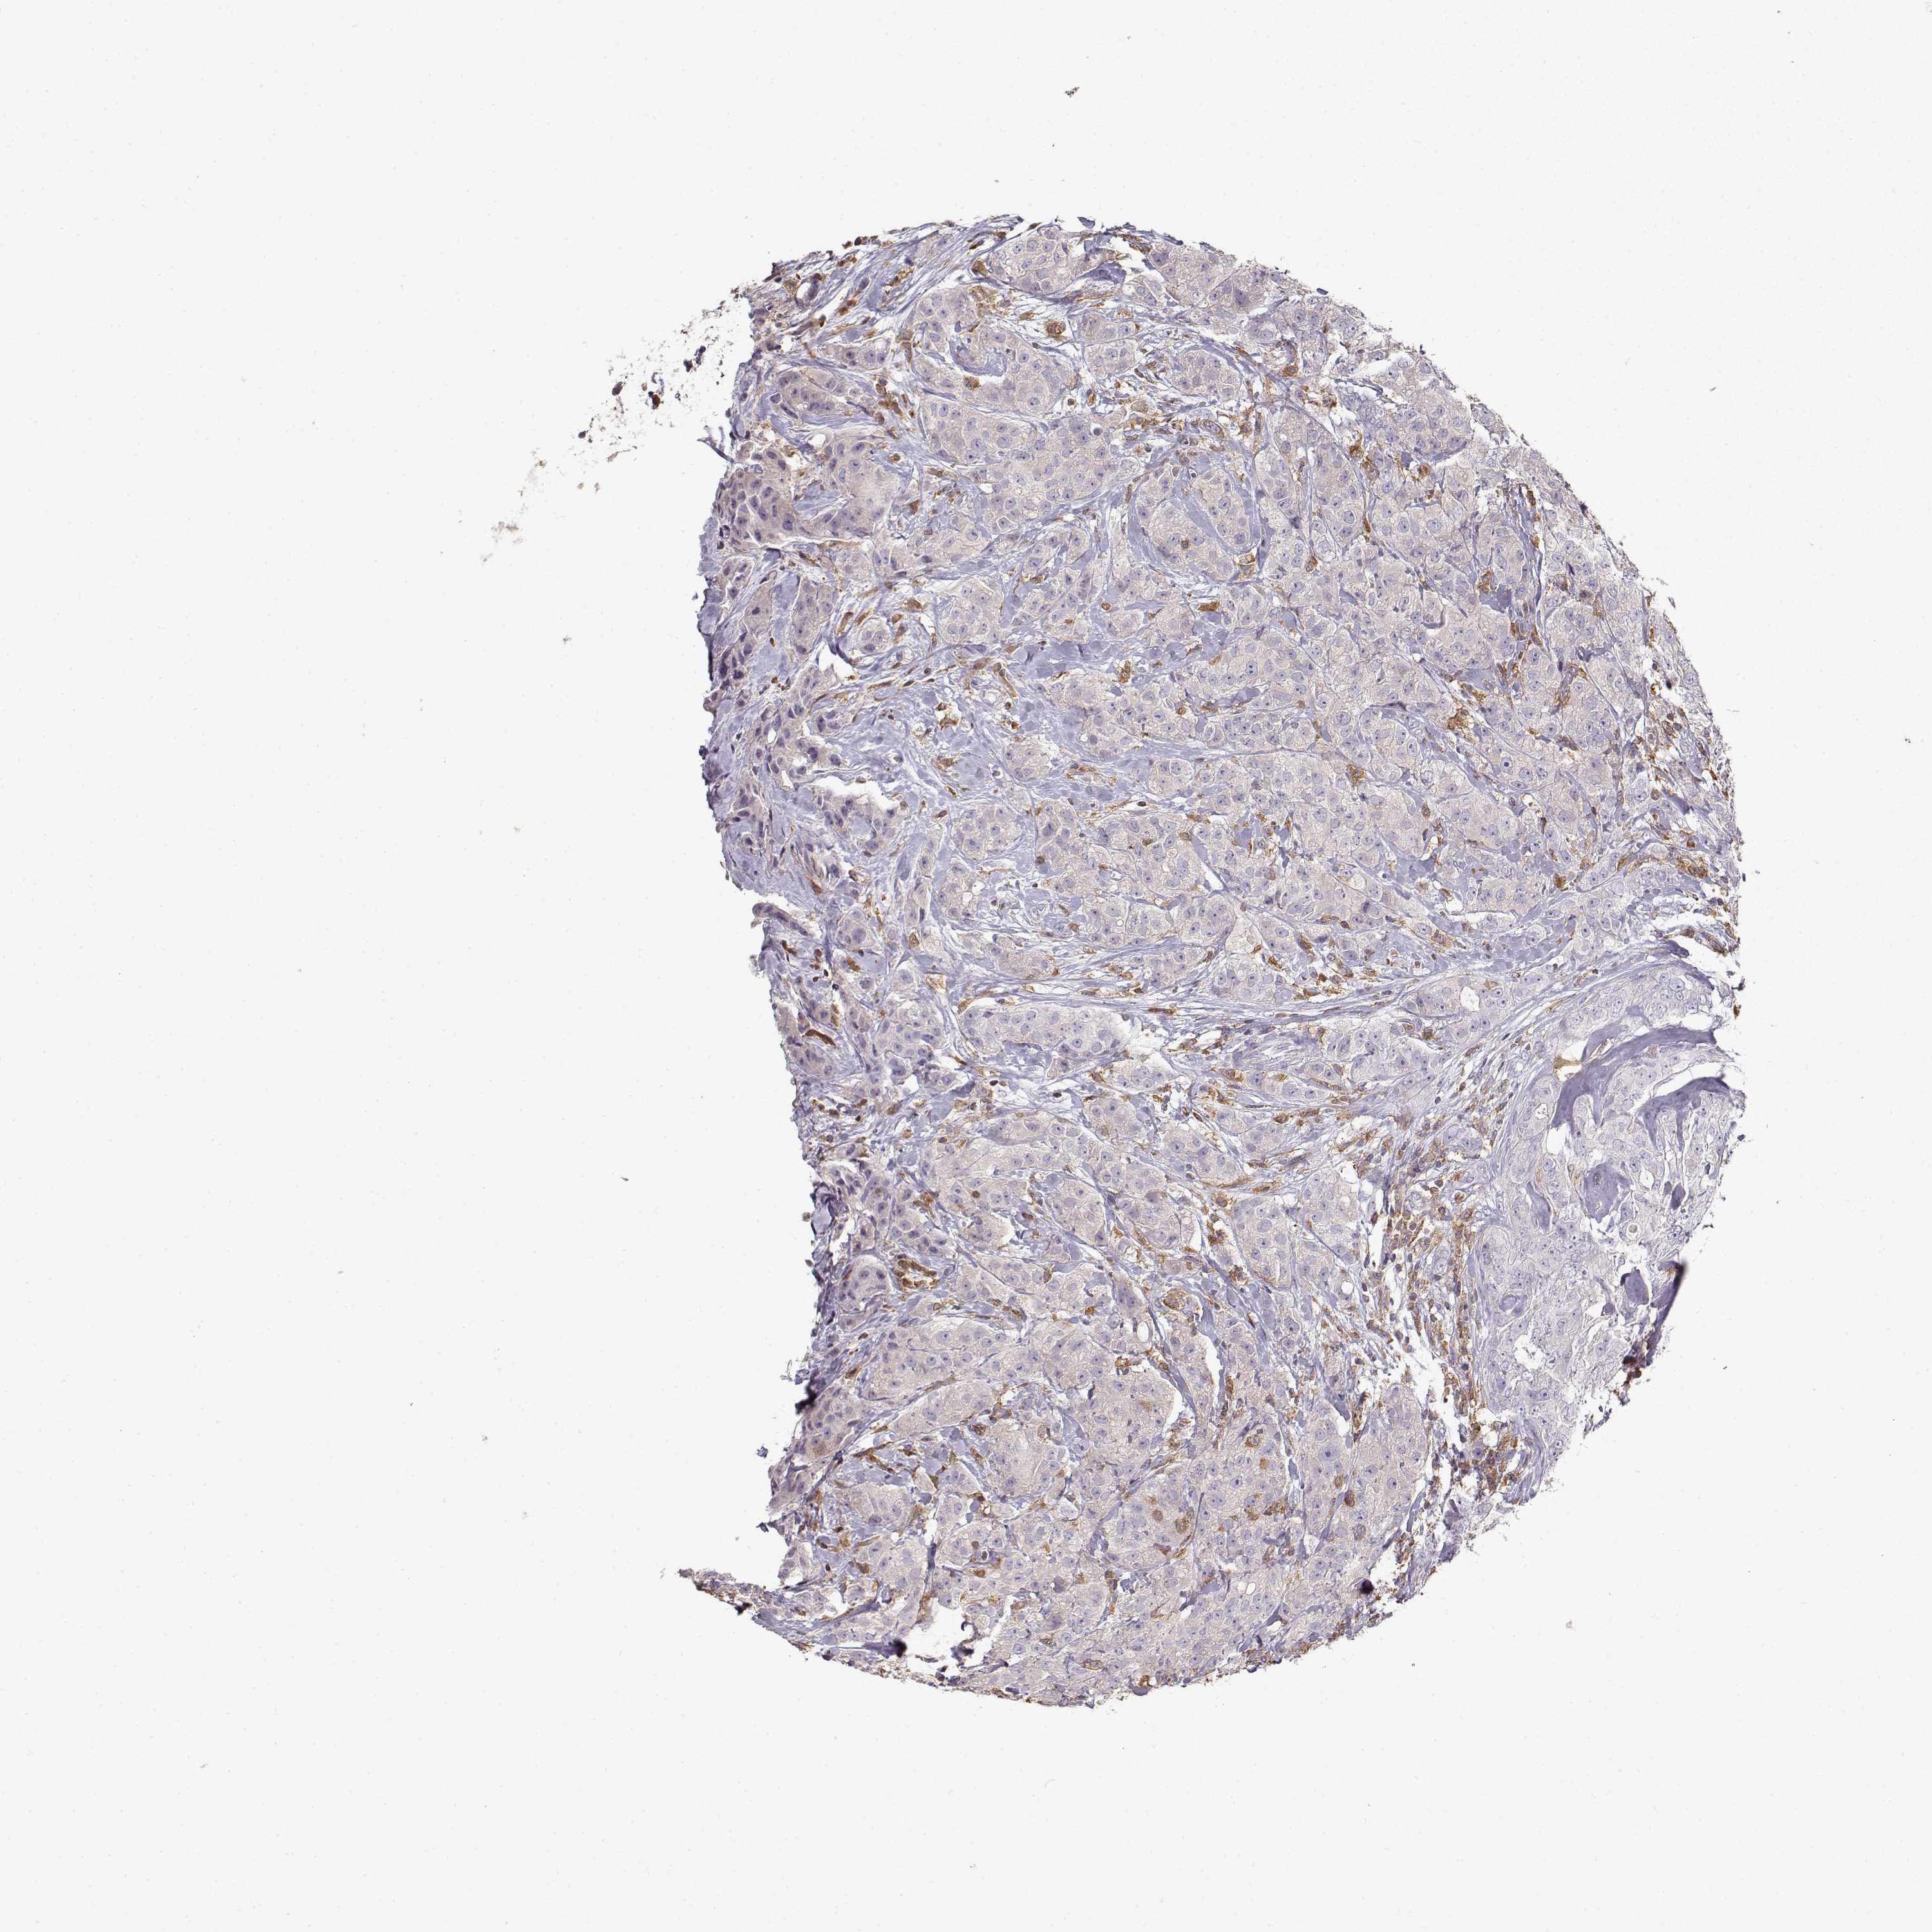

CANCER BREAST CANCER Show tissue menu

BRCA TCGA BRCA VALIDATION PROTEIN EXPRESSION